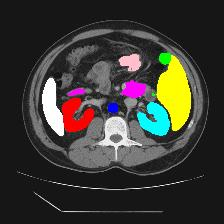

Medical image segmentation is one of the most fundamental tasks concerning medical information analysis. Various solutions have been proposed so far, including many deep learning-based techniques, such as U-Net, FC-DenseNet, etc. However, high-precision medical image segmentation remains a highly challenging task due to the existence of inherent magnification and distortion in medical images as well as the presence of lesions with similar density to normal tissues. In this paper, we propose TFCNs (Transformers for Fully Convolutional denseNets) to tackle the problem by introducing ResLinear-Transformer (RL-Transformer) and Convolutional Linear Attention Block (CLAB) to FC-DenseNet. TFCNs is not only able to utilize more latent information from the CT images for feature extraction, but also can capture and disseminate semantic features and filter non-semantic features more effectively through the CLAB module. Our experimental results show that TFCNs can achieve state-of-the-art performance with dice scores of 83.72\% on the Synapse dataset. In addition, we evaluate the robustness of TFCNs for lesion area effects on the COVID-19 public datasets. The Python code will be made publicly available on https://github.com/HUANGLIZI/TFCNs.

翻译:医学图像分解是医学信息分析的最根本任务之一,到目前为止已经提出了各种解决办法,包括许多深层次的学习技术,如U-Net、FC-DenseNet等。 然而,高精度医学图像分解由于医疗图像中存在固有的放大和扭曲,以及存在与正常组织密度相似的损伤,因此仍是一项极具挑战性的任务。在本文件中,我们建议TFCN(全面革命稠密网络的传输者)通过向FC-DenseNet引进ResLear-Transerferent(R-Transerfor)和Culvacial线性关注区(CLAB)来解决这一问题。TFCN不仅能够利用CT图像中更多的潜在信息来提取特征,而且还能够通过CLAB模块更有效地捕捉和传播语性特征和过滤非神经性特征。我们的实验结果表明,TFCN可以在Syapseion/SymblyDDS上以83CN-72 ⁇ 的分数实现状态。此外,我们在Synapse-DRIS数据设置上,我们还将评估CUTFTFI/LIS的可靠度。